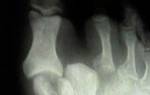

Обычно пациенту назначают рентгенографию, на которой хорошо видно наличие вывиха. Если ситуация осложняется разрывом связок и сухожилий или требуется оценка структуры сустава и окружающих мышц, понадобится более современное оборудование, такое как компьютерная томография или магнитно-резонансная томография. Эти процедуры также предпочтительны, если пациенту требуется операция.

Для исключения перелома врач может назначить рентген, но часто достаточно обычного осмотра и опроса пациента.